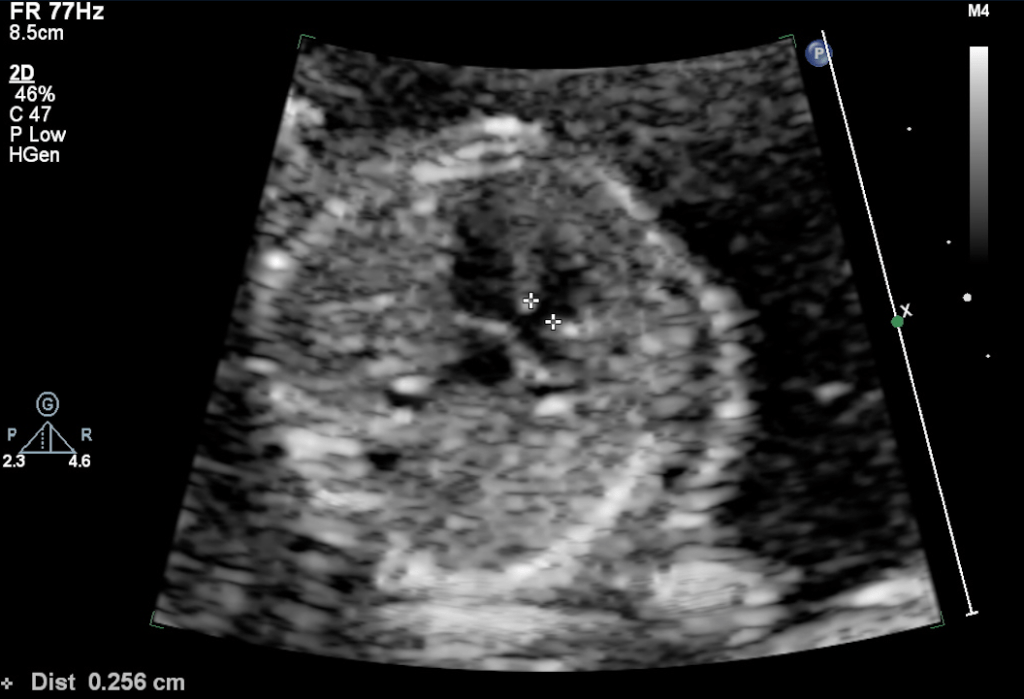

Smaller VSDs are much more common than a large defect. Also, the smaller defects are much more difficult to diagnose in early pregnancy fetal echocardiography because both the ventricle has similar pressures. Thus there is no significant color doppler flow can be seen across small VSD during most of the cardiac cycle. The 2D echo image also can miss a small VSD because of pixel spread of image due to significant magnification used during the echo.

The classification of Large or small VSD is entirely arbitrary, and no classification has been given. From some earlier studies, the outcome has been studied as <3mm and >3 mm size, and closure rate has shown to be different in these two groups. So, it may be fair to use this as classifying the size of the VSD into two groups, viz. small and large VSD. The other criteria used is the ratio of the size of the defect with the annulus size of Aorta. VSD/aorta ratio<0.5 is considered small, and VSD/aorta ratio>0.5 is deemed to be large. Although in many instances there are muscular defects with are seen as definite color drop-out but on 2-D image not measurable, such a defect can be labeled as tiny or very small VSDs or small VSD of < 1mm.